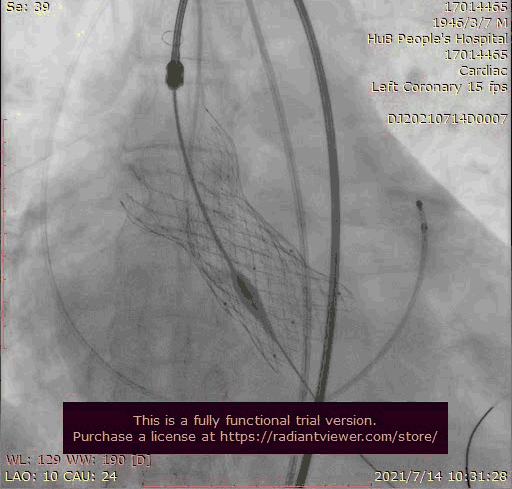

使用venus-A plus回收后重新定位释放

瓣膜位置尚可

大结构瓣膜稳定性差,输送器使瓣膜跳到瓣上

奇思妙想使用射频消融大头压住支架至窦底

在大头压迫支架下释放第二个瓣膜

第二个支架完美释放固定第一个支架

1.在第一次释放瓣膜时,由于患者主动脉根部瓣上瓣下均比瓣环平面大,受到血流的冲击,瓣膜滑至较深的位置,使用venus-A PLUS回收

2.回收后重新定位释放,由于第一次滑至较深,第二次稍微卸力后瓣膜跳至窦上,使用venus-A PLUS回收,再次重新定位

3.第三次释放瓣膜后位置的把控非常精准,瓣膜位置合适,但由于稳定性差,撤出输送系统时瓣膜跳至窦上,此时非常凶险,瓣膜无法固定住,受到血流的冲击,可能对升主造成夹层的风险,一般会选择开胸取出,但风险非常,在江洪教授的思考下和团队的讨论下,决定使用射频消融大头穿过支架网孔使瓣膜到窦底固定,在此基础上释放第二个瓣膜,使用第二个瓣膜花冠固定住第一个瓣膜

4.第四次瓣膜释放后两个瓣膜均稳定住,造影超声评估无瓣周漏,二尖瓣反流也基本消失,观察一小时后,无其他情况。患者顺利下台